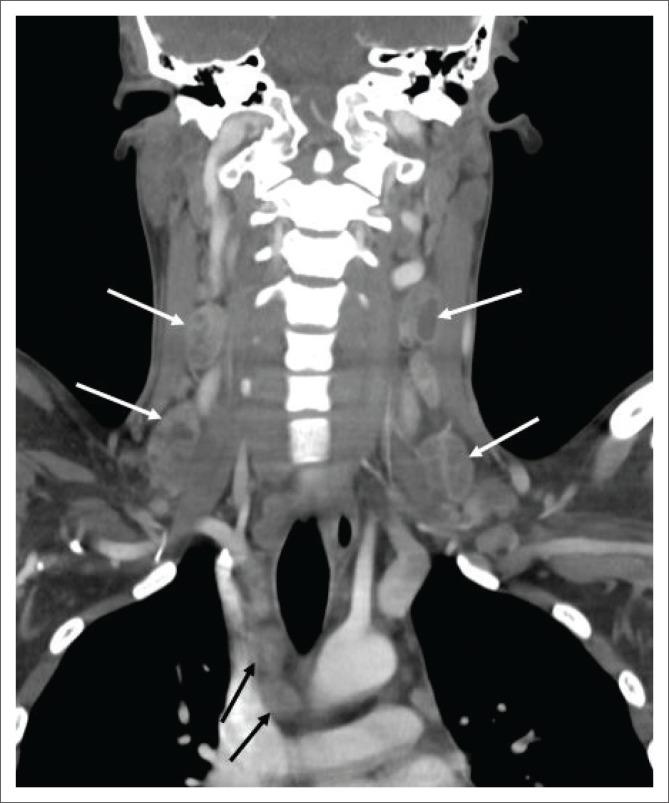

Extra-pulmonary tuberculosis (EPTB), caused by , is the leading cause of communicable disease-related deaths in people with human immunodeficiency virus (HIV) worldwide and in South Africa. disseminates haematogenously from an active primary lung focus and may affect extra-pulmonary sites in up to 15% of patients. Extra-pulmonary TB may present with a normal chest radiograph, which often causes a significant diagnostic dilemma. This review describes the main sites of involvement in EPTB, which is illustrated by local imaging examples.

由……引起的肺外结核病(EPTB)是全球和南非人类免疫缺陷病毒(HIV)感染者中与传染病相关死亡的主要原因。……从活跃的原发性肺部病灶经血行播散,高达15%的患者可能累及肺外部位。肺外结核病可能胸部X线片表现正常,这常常造成重大的诊断困境。本综述描述了肺外结核病的主要受累部位,并通过局部影像学实例进行说明。 (注:原文中“caused by ”和“disseminates haematogenously from an active primary lung focus and may affect extra-pulmonary sites in up to 15% of patients.”前缺失关键信息)